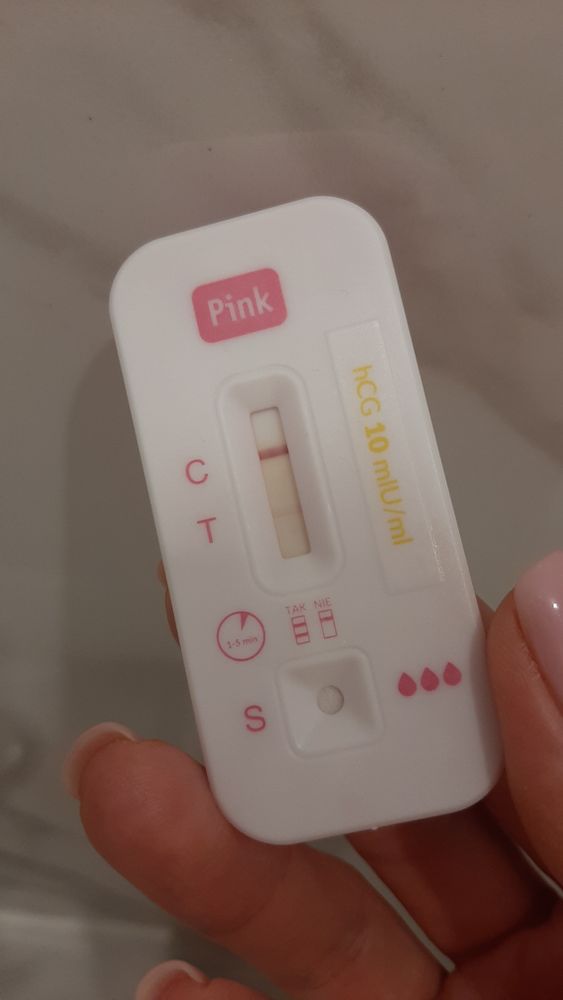

Беременность или нет?! Фото узи.

Всем привет! У кого так было. На узи не видно плодное яйцо. Не ясно беременность или нет. Тест показал +. Все симптомы беременности есть. Может ещё совсем маленький срок?

Barbie , с такой полосочкой конечно узи ничего не увидит, там ещё точка с маковое зёрнышко🙏🏻 не переживайте, все у вас в порядке🌹

На узи раньше 1500 хгч идти смысла нет особо, это при стандартной овуляции 7-8 день задержки.

Екатерина, тест положительный. Делала тесты 4 дня назад и ХЧГ были отрицательные. А в субботу показал + тест

Barbie , ну так зачем тогда в панику впадаете? Тест бледный, там ХГЧ ещё и сотни нет, при таком ХГЧ ничего не увидеть. Дней через 7 пя, а сб и того позже.